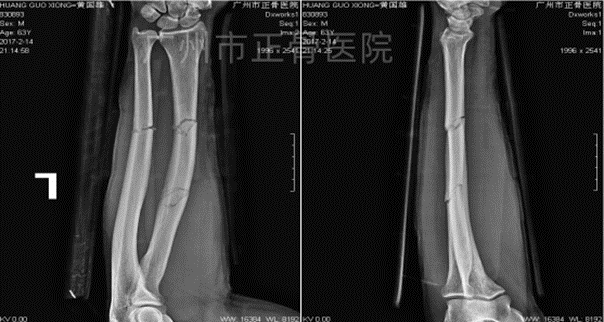

▲2个月后,骨折线模糊,拆除夹板

▲1年后,骨性愈合